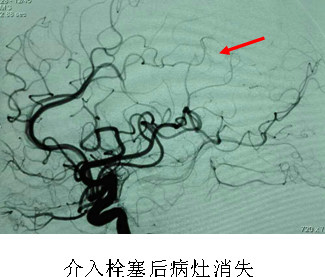

患者王某,女性,54岁,因左侧顶枕叶脑出血收住入院,既往无高血压病史,病情稳定后经DSA检查现已明确为左侧顶叶脑动脉静脉畸形;另一患者肖某,女性,74岁,因自发性蛛网膜下腔出血收住入院,经本次手术检查已明确为右侧大脑后动脉动脉瘤。两名患者通过本次手术均很快找到出血病因,为后续治疗指明方向及制定治疗方案提供了可靠依据。

这两台手术的顺利完成,标志着我院神经外科在脑血管疾病的诊断及诊治方面进入了一个新的阶段,同时也是大丰地区该项新技术零的突破,再一次显示了我院整体医疗实力的显著提高。我院也将不断创新,大力开展新技术、新项目,更好地为大丰人民提供优质的医疗服务。